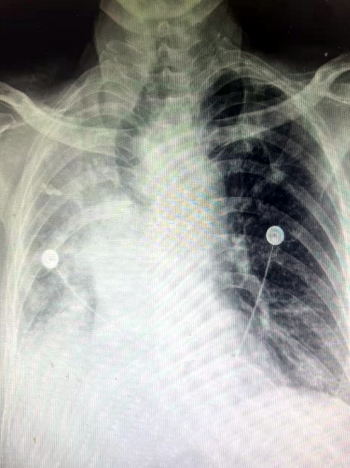

在患者入院后,呼吸与危重症医学科对患者进行了进一步检查。在高流量吸氧80%条件下,患者静息氧饱和度仅能维持在80-85%左右,床旁胸片显示右肺完全不张可能,呼吸与危重症医学科介入团队评估后,决定立即进行急诊手术准备。一方面与家属积极沟通,交代病情和风险,另一方面与麻醉科、微创手术平台联系,做好各环节衔接准备,并沟通抢救预案。2025年5月23日上午,手术在微创中心(第二手术区)正式开始。入室时,患者血氧饱和度仅有68%,伴有神志淡漠,意识恍惚。麻醉师迅速给予全麻,呼吸介入团队马上进行进镜探查。镜下发现患者右主支气管被肿物完全阻塞,伴有血性分泌物。在微创手术室护士的配合下,呼吸介入团队用电圈套器、电刀、冷冻冻切等多种方法,迅速打通了气道。经过45分钟的手术,患者氧饱和度已恢复至97%。手术成功。

术前胸片